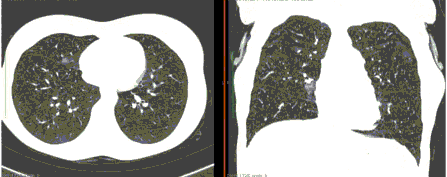

КТ имеет высокую чувствительность в выявлении изменений в легких, характерных для COVID-19. Применение КТ целесообразно для первичной оценки состояния ОГК у пациентов с тяжелыми прогрессирующими формами заболевания, а также для дифференциальной диагностики выявленных изменений и оценки динамики процесса. КТ позволяет выявить характерные изменения в легких у пациентов с COVID-19 еще до появления положительных лабораторных тестов на инфекцию с помощью МАНК. В то же время, КТ выявляет изменения легких у значительного числа пациентов с бессимптомной и легкой формами заболевания, которым не требуется госпитализация. Результаты КТ в этих случаях не влияют на тактику лечения и прогноз заболевания при наличии лабораторного подтверждения COVID-19. Поэтому массовое применение КТ для скрининга асимптомных и легких форм болезни не рекомендуется. При первичном обращении пациента с подозрением на COVID-19 рекомендуется назначать КТ только при наличии клинических и инструментальных признаков дыхательной недостаточности (SpO2 < 95%, ЧДД > 22).

3. Применение лучевых методов у пациентов с симптомами ОРВИ легкой степени тяжести и стабильном состоянии пациента, возможно только по конкретным клиническим показаниям, в том числе при наличии факторов риска, при условии достаточных технических и организационных возможностей. Методом выбора в этом случае является КТ легких по стандартному протоколу без внутривенного контрастирования или РГ при ограниченной доступности КТ. Использование УЗИ в этих случаях нецелесообразно. Применение КТ исследования в сроки ранее 3 - 5 дней с момента появления симптомов заболевания, а также при отсутствии клинических проявлений поражения бронхолегочной системы является нецелесообразным. Выполнение КТ целесообразно при наличии клинических и инструментальных признаков дыхательной недостаточности (SpO2 < 95%, ЧДД > 22), либо при дифференциальной диагностике с другим заболеванием.

4. Все выявляемые при лучевых исследованиях признаки, включая КТ-симптомы, не являются специфичными для какого-либо вида инфекции и не позволяют установить этиологический диагноз. Вне клинической (эпидемической) ситуации они не позволяют отнести выявленные изменения к пневмонии COVID-19 и дифференцировать их с другими пневмониями и невоспалительными заболеваниями. Данные лучевого исследования не заменяют результаты обследования на РНК SARS-CoV-2. Отсутствие изменений при КТ не исключают наличие COVID-19 и возможность развития пневмонии после проведения исследования.